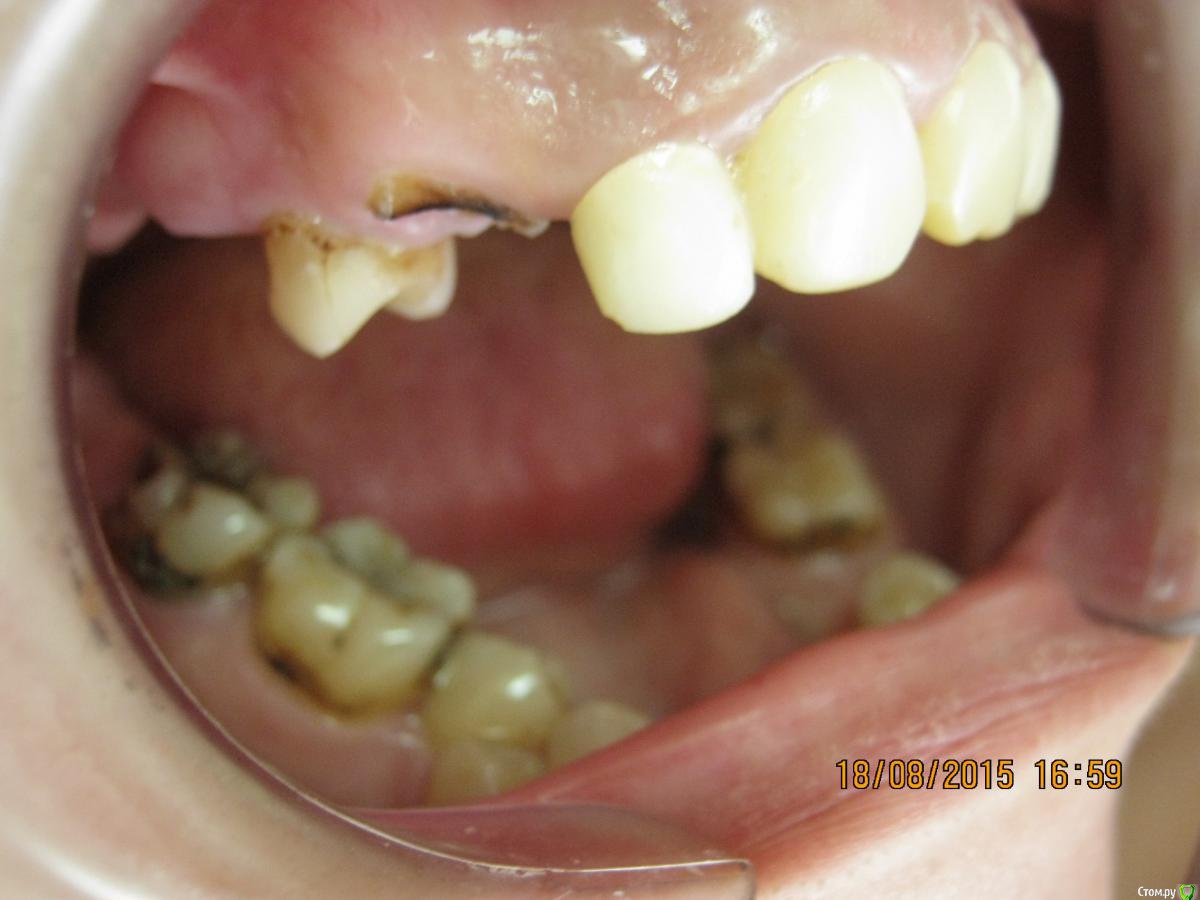

SeregaStomatolog Опубликовано 18 августа, 2015 Поделиться Опубликовано 18 августа, 2015 Добрый вечер уважаемые коллеги!В клинику обратилась пациентка с такой ситуацией во рту.Подскажите пожалуйста что можно сделать и с чего начать. Ссылка на комментарий

SeregaStomatolog Опубликовано 18 августа, 2015 Автор Поделиться Опубликовано 18 августа, 2015 Во-первых она хочет нормально улыбаться,не стесняясь отсутствующего клыка.Во-вторых она хочет нормально жевать,т.к. отсутствие 1.7,1.6 не позволяет это делать.Я сразу сказал пациентке что вариантов без ортодонтии мало (если они вообще есть) и обещать ничего не стал.Случай сложный,поэтому хочется узнать в принципе,на будущее,какие варианты лечения возможны (если можно по подробнее).Пока что я снял слепки,отлил модели-пошел за советом к коллегам в другую клинику-все настаивают на ортодонтии.Теперь вся надежда на Вас коллеги,подскажите что можно придумать более менее приемлемое без ортодонтии. Ссылка на комментарий

SeregaStomatolog Опубликовано 18 августа, 2015 Автор Поделиться Опубликовано 18 августа, 2015 Сделав как хочет пациентка вы не получите красивый результат, которого она ждет! и получится что вы не смогли реализовать ее мечты , а значит доктор неахти)) да и вы не особо результатом будете довольны, вам это надо? Если в эстетике проблем нет, восстановите функцию. Ненужное удалить, длинные зубы дэпульпировать, укоротить ну и коронуйте))Мне кажется если я возьмусь,то все равно не буду результатом доволен,т.к. все реализовать не получится.Самая большая проблема в области отсутствующих 1.6,1.7-зубо-альвеолярное удлинение 4.6,4.7 настолько велико,что они практически касаются слизистой в области 1.6,1.7. Ссылка на комментарий